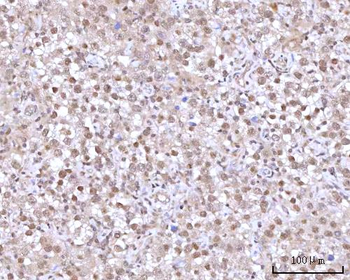

IHC staining of FFPE human lymph node with CD72 antibody (clone BU40). HIER: boil tissue sections in pH9 10mM Tris with 1mM EDTA for 20 min and allow to cool before testing.

IHC staining of FFPE human lymph node with CD72 antibody (clone BU40). HIER: boil tissue sections in pH9 10mM Tris with 1mM EDTA for 20 min and allow to cool before testing.